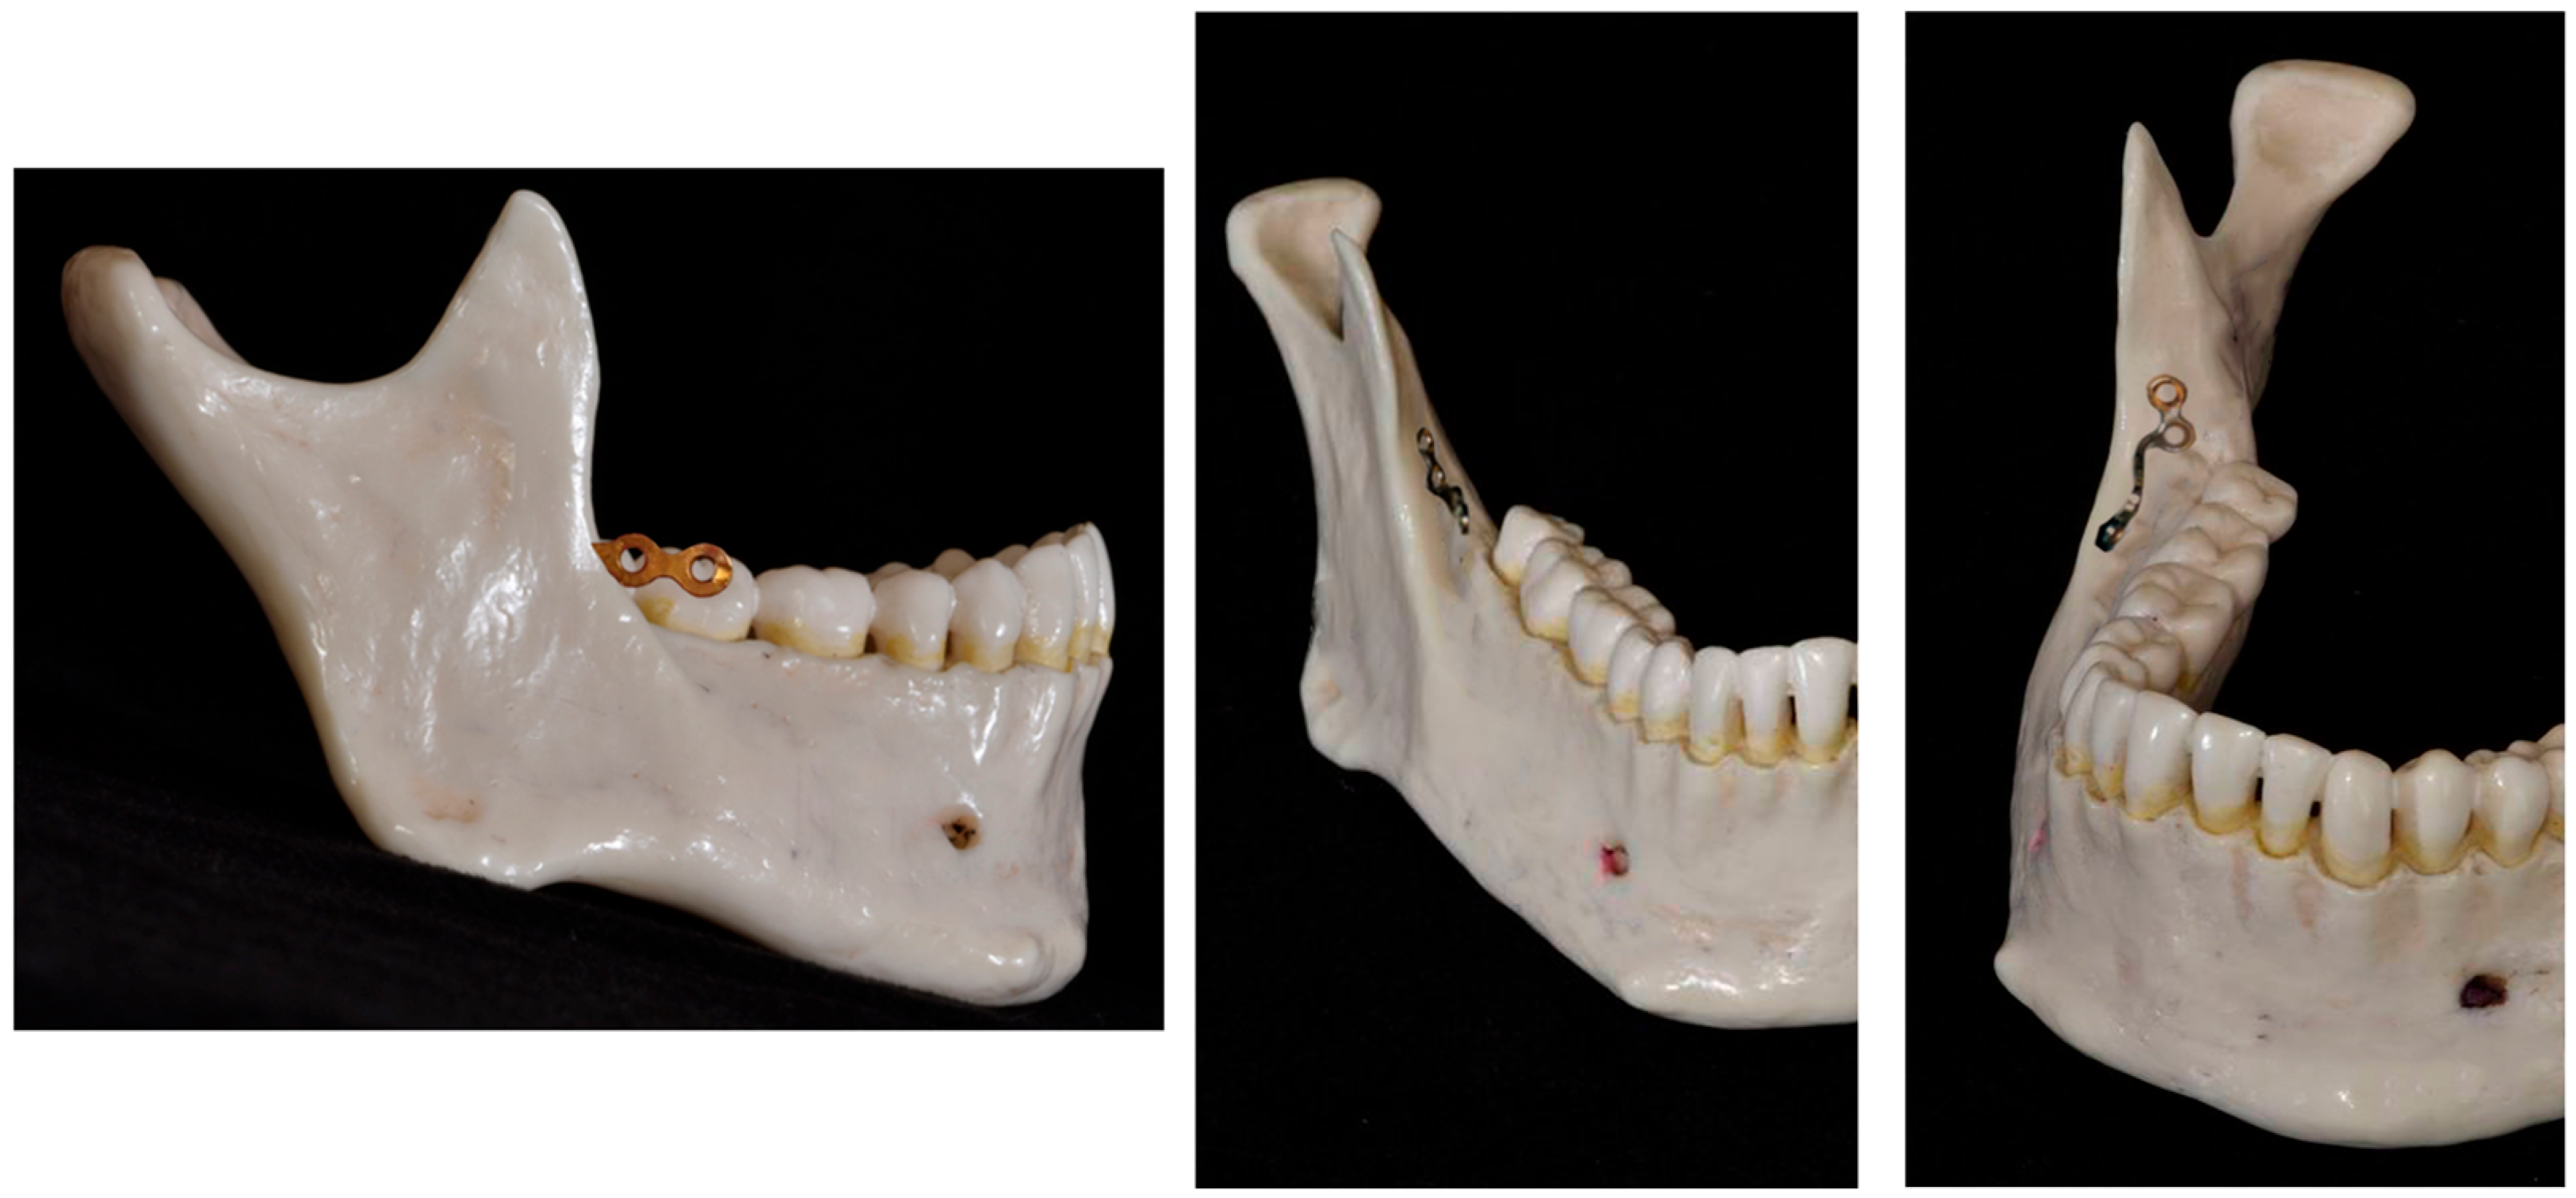

- Yu, J.; Park, J.H.; Bayome, M.; Kim, S.; Kook, Y.-A.; Kim, Y.; Kim, C.-H. Treatment effects of mandibular total arch distalization using a ramal plate. Korean J. Orthod. 2016, 46, 212–219. [Google Scholar] [CrossRef]

- Kook, Y.-A.; Park, J.H.; Bayome, M.; Kim, S.; Han, E.; Kim, C.H. Distalization of the mandibular dentition with a ramal plate for skeletal Class III malocclusion correction. Am. J. Orthod. Dentofac. Orthop. 2016, 150, 364–377. [Google Scholar] [CrossRef]